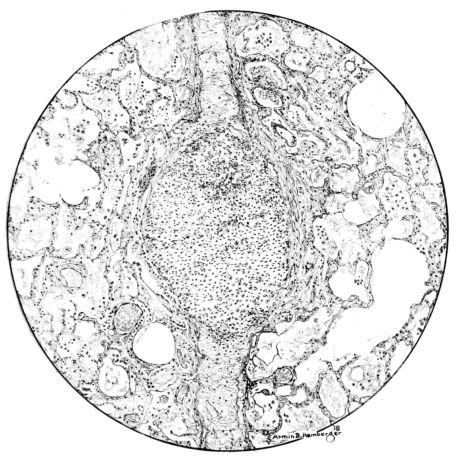

FIG. II. AUTOPSY NO. 98. DRAWING OF A SECTION THROUGH A TRACHEA SHOWING NECROTIZING HEMORRHAGIC INFLAMMATORY PROCESS OF THE MUCOSA.

The changes are less marked, perhaps, in the trachea than in its finer ramifications. The mucosa is constantly more or less destroyed and large areas, usually focal, are entirely devoid of their epithelial covering. This is replaced by a sparse exudate, composed largely of red blood cells, mucus, a small amount of fibrin, and nuclear fragments (Fig. II). It may dip into the submucosa for a short distance, but usually these indentures are associated with the ducts of the mucous glands into which the inflammatory reaction extends. A more striking feature than the exudate, however, is the edema and the congestion of the submucosa. The loose areolar tissue of the submucosa is spread widely apart, and throughout it distended blood vessels are very conspicuous. Occasionally such a vessel is broken and actual hemorrhage appears in the submucosa. Occasionally, too, the inflammation extends down the duct to the mucous gland itself, and here, also, aplastic inflammatory reaction is evident, inasmuch as the acini now stain intensely red with the cells undifferentiated from each other and specked here and there by broken remains of the dead nuclei (Fig. III). After the disease has continued for a short period, even at the end of five or six days, some regeneration of the epithelial lining may be seen (3) (Fig. IV). But despite this, the acute picture persists, and there goes on, side by side, an attempted repair characterized by epithelial regeneration and the same evidence of acute change. Since the lesion is essentially a superficial one, scars or contractures of any extent are not encountered in the trachea, even in examples of the disease that have ended fatally only after many weeks.[4]